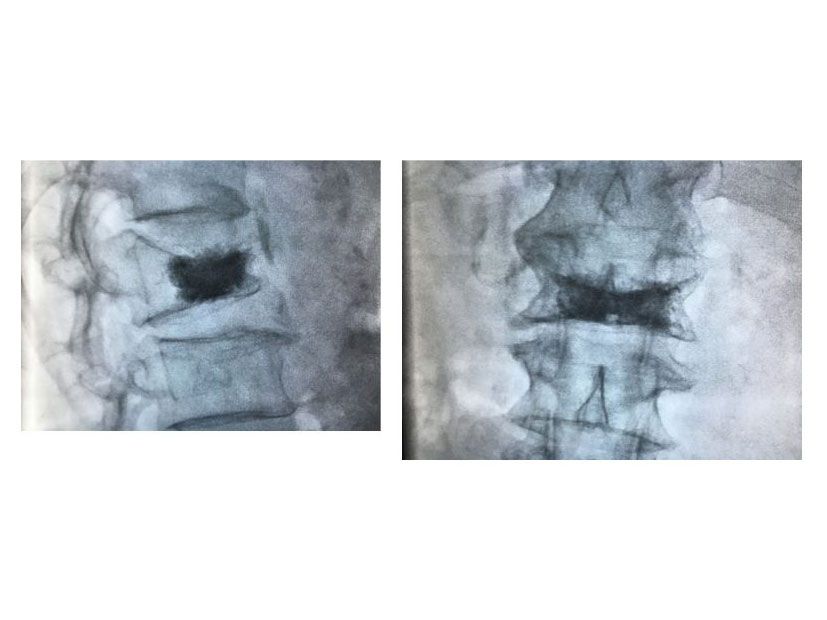

Vertebroplasty

Vertebroplasty / Vertebral body stenting